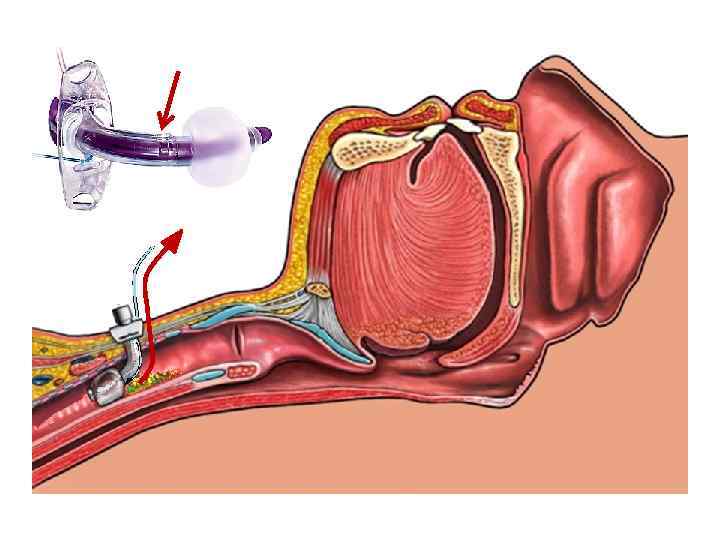

Профилактика и лечение инфекционновоспалительных изменений гортани и верхних отделов трахеи Дренаж надманжеточного пространства Portex

Профилактика и лечение инфекционновоспалительных изменений гортани и верхних отделов трахеи Дренаж надманжеточного пространства Portex

Канал для санации надманжеточного пространства

Канал для санации надманжеточного пространства

Борьба с аспирацией «обычные» трубки Каналы в складках манжетки? это плохо!!!

Борьба с аспирацией «обычные» трубки Каналы в складках манжетки? это плохо!!!

Борьба с аспирацией «особенные» трубки Каналы в Новейшие технологии, складках лучшие материалы и борьба за рынок манжетки?

Борьба с аспирацией «особенные» трубки Каналы в Новейшие технологии, складках лучшие материалы и борьба за рынок манжетки?